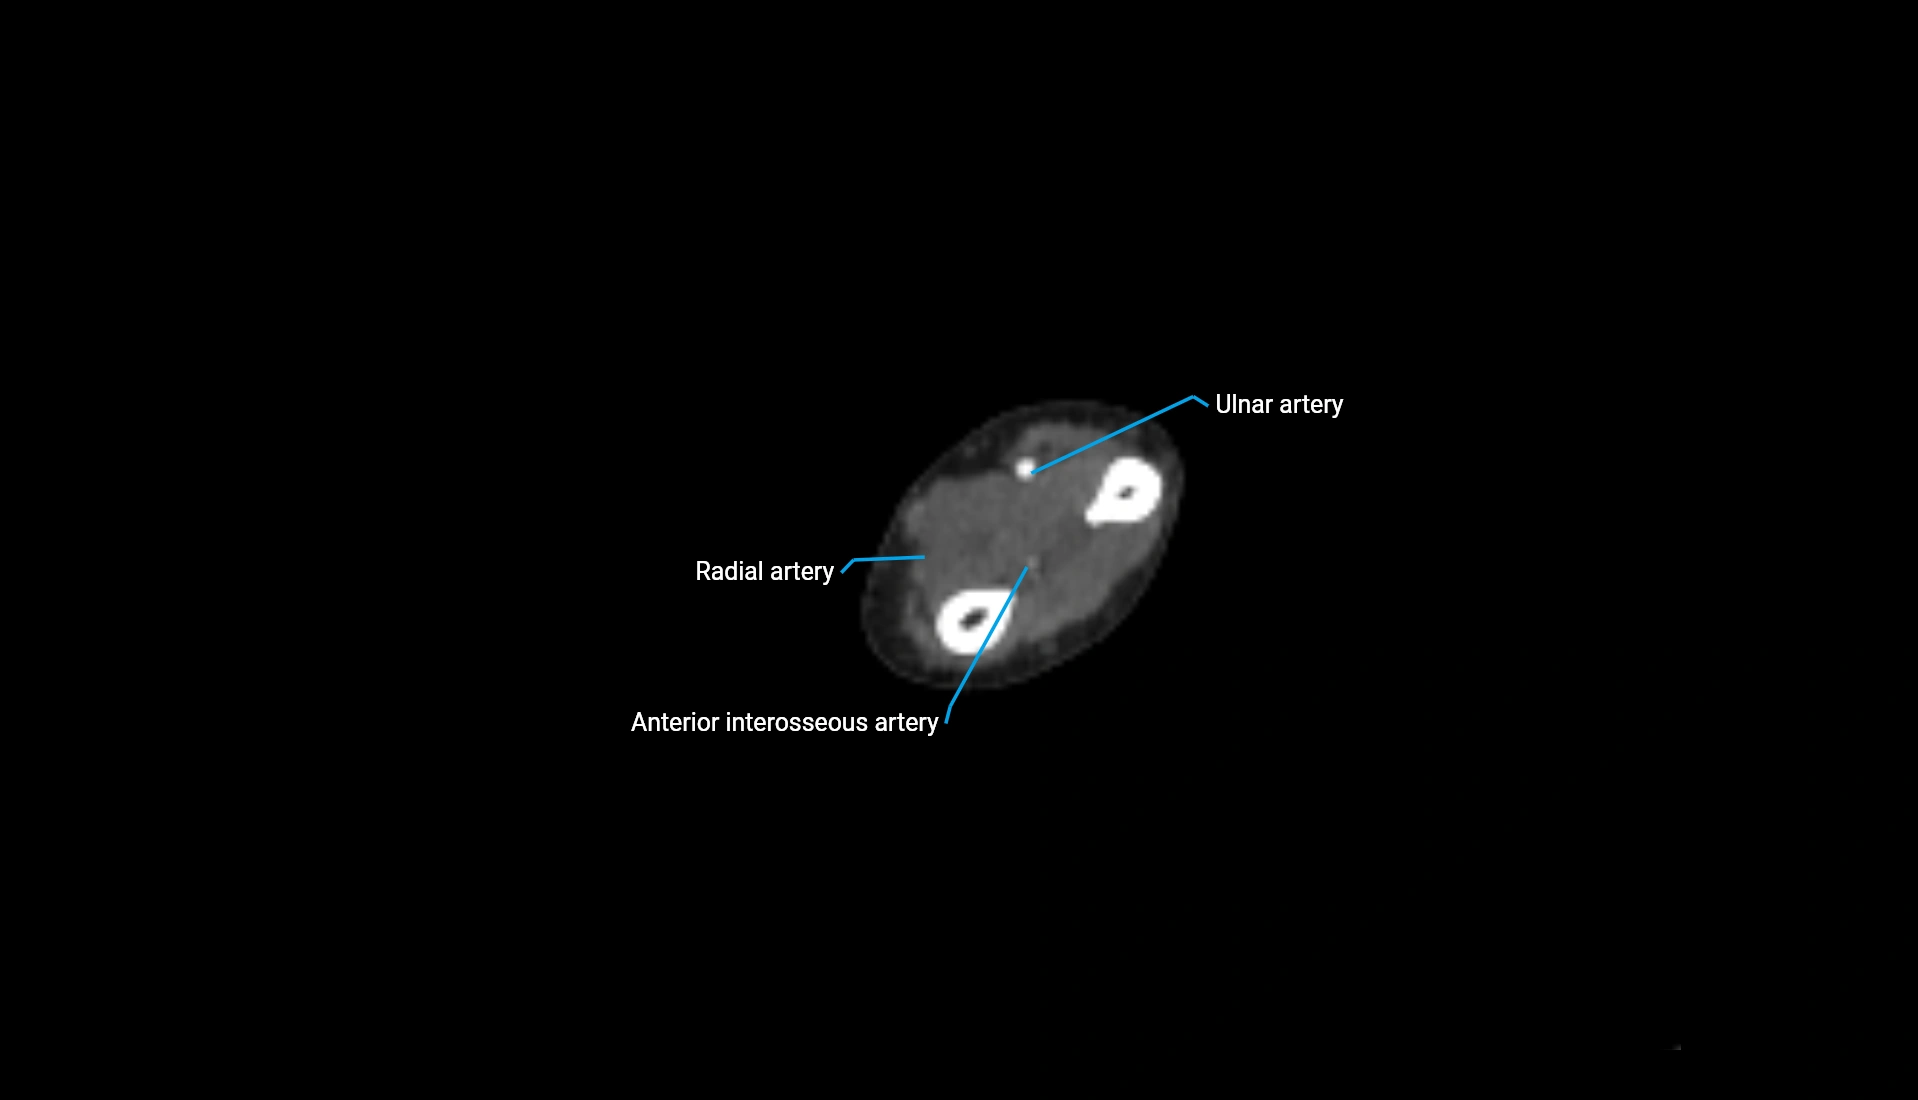

CT Appearance

Non-Contrast CT:

• Cortex: High-density, sharply defined

• Subchondral bone: Dense cancellous matrix

• Articular surface: Smooth concave contour articulating with the capitellum

• Excellent for evaluating bone integrity, alignment, and subtle fractures

Post-Contrast CT:

• Bone: No enhancement

• Joint capsule and synovium: Mild enhancement outlining the joint

• Improves contrast between soft tissues and bony margins

• Useful in detecting subtle joint abnormalities or postoperative changes